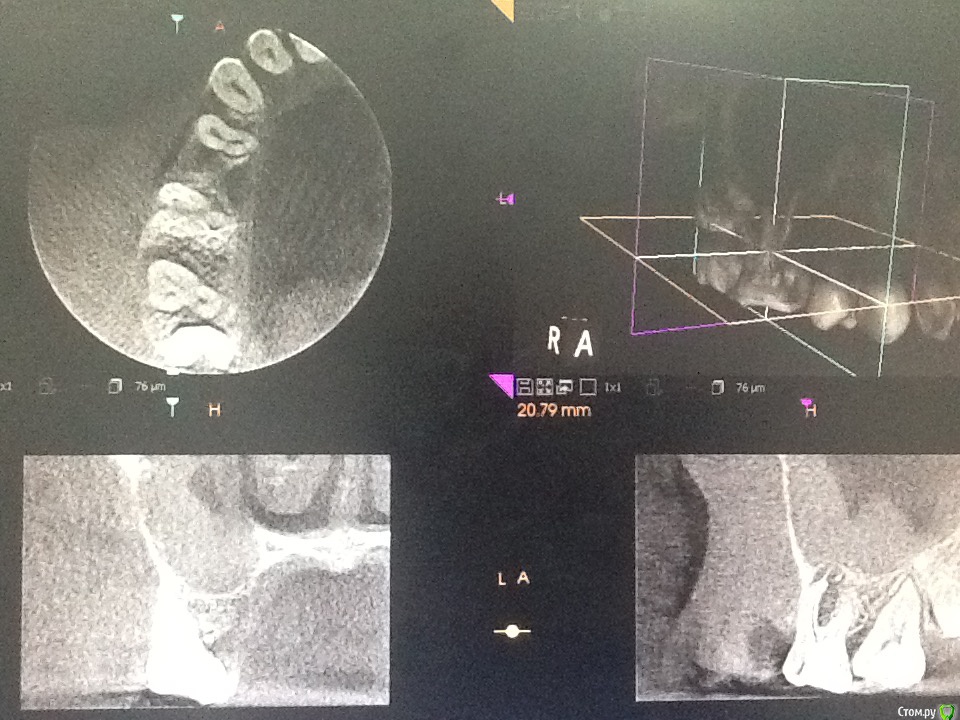

diesel87 Опубликовано 24 ноября, 2015 Поделиться Опубликовано 24 ноября, 2015 Спрошу у терапевтов, сегодня пришла пациентка полечить пульпит в 14, полечили, принесла с собой орто, посмотрел, забавная гранулема в пазухе выросла, причина видимо 16, есть подвижность 1 степени, со стороны неба отмечает периодические выбухания, которые сами проходят. Думаю ей 12 лет, не пациентке. Что скажите господа, эндо имеет смысл? http://fs5.directupload.net/images/151124/2hrfb9kp.jpg http://fs5.directupload.net/images/151124/nf6tk9pj.jpg Ссылка на комментарий

Л Ю С Я Опубликовано 24 ноября, 2015 Поделиться Опубликовано 24 ноября, 2015 Надо кт, может и не связано с зубом Ссылка на комментарий

DmitrySH Опубликовано 24 ноября, 2015 Поделиться Опубликовано 24 ноября, 2015 КТ надо бы, делать эндо, но в голове держать план возможной хирургической реабилитации.14, тоже гранулема. 1 Ссылка на комментарий

diesel87 Опубликовано 24 ноября, 2015 Автор Поделиться Опубликовано 24 ноября, 2015 КТ надо бы, делать эндо, но в голове держать план возможной хирургической реабилитации.14, тоже гранулема.с 14 все норм Ссылка на комментарий